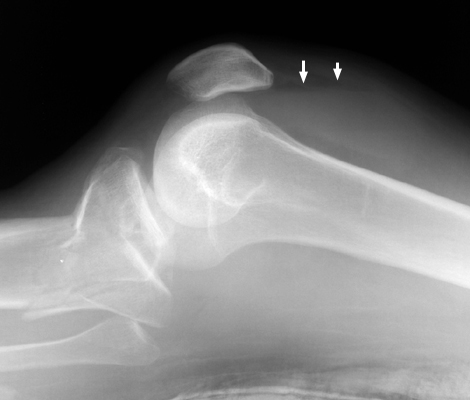

Lipohemarthrosis

Fat fluid interface seen on the multiple lateral radiographs of the knee secondary to lipohemarthrosis. The fat-blood interface (FBI) is a very suggestive sign of underlying fracture extending into the joint. If no fracture is readily identified, diligent search should be undertaken.

Cross table lateral knee - Click on the image for a larger versionACross table lateral - Click on the image for a larger versionB